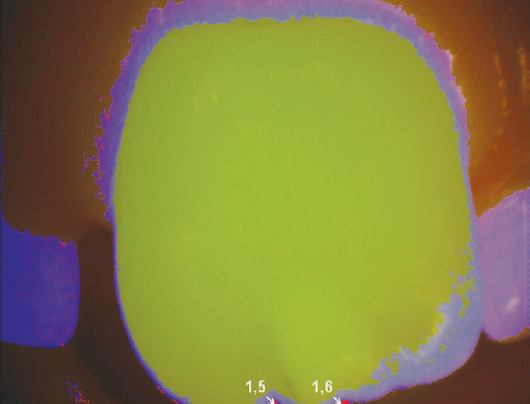

Oral cavity sanitation was performed in all patients before and during the installation of the bracket system and the stages of treatment. The average treatment period was no longer than 30 months. Caries intensity was assessed after oral cavity sanitation. The “D” component included caries in staining stage K02.0. Noncarious enamel defects, classified in ICD10 under codes K00.4 and K00.5, were also noted. Patients with confirmed diagnoses of dental fluorosis (K00.30) were excluded according to the criteria. The differential diagnosis between carious and noncarious stains was made using vital staining and fluorescence diagnostics after plaque removal. If staining was not detected and porphyrin fluorescence was absent, enamel defects (K00.4 and K00.5) were noted. If staining was detected and porphyrin fluorescence was present, caries (K02.0) was noted. Methylene blue solution was used for staining, and VistaCam was used to determine fluorescence (Figs. 1 and 2).

Fig. 1. Spot without signs of demineralization; enamel hypomineralization of noncarious origin (postnatal hypoplasia, K00.4)

Рис. 1. Пятно без признаков деминерализации — гипоминерализация эмали некариозного происхождения (постнатальная гипоплазия К00.4)

Fig. 2. Stain with signs of demineralization in the subsurface layer (caries, K02.0)

Рис. 2. Пятно с признаками деминерализации в подповерхностном слое (кариес К02.0)